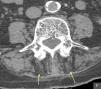

The patient is an 86-year-old male, who performed activities of daily living independently and a history of ischemic heart disease, chronic atrial fibrillation, diabetes mellitus type I and hypothyroidism. He consulted due to back pain and mechanical instability, without previous trauma. It was accompanied by a harmonic progressive kyphosis, reductible when upright and recumbent. The physical examination showed increased anteroposterior curvature of the spine, which conditioned contact of the ribs to the pelvis and was reduced when prone (Fig. 1), with slight flexion of the knees and retroversion of the pelvis. The remaining physical examination was unremarkable. Radiographs were performed and on the lumbar spine (anteroposterior and lateral) showed no significant alterations except for degeneration. With the suspected diagnosis of camptocormia, we requested a CT scan of the lumbar spine which showed selective posterior paravertebral muscle atrophy (Fig. 2), consistent with the initial workup. Analgesic treatment and rehabilitation was started.

The diagnosis is clinical, supported by additional tests such as a CT scan of the lumbar and dorsal column, which typically shows hypodensity and atrophy of the paravertebral muscles and is interpreted as an involution of fat. Given the heterogeneous etiology of this disorder, other examinations such as an electromyogram may be performed; hormonal, bone metabolism and muscle enzymes studies, cranial computed tomography and/or MRI to study basal ganglia may be affected in patients with Parkinson's camptocormia. Patients may also undergo a muscle biopsy.1